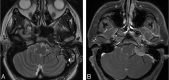

Background and purpose: The purpose of this work was to study differences in apparent diffusion coefficient (ADC) values between benign and malignant head and neck lesions at 3T field strength imaging.

Materials and methods: Our study population in this retrospective study was derived from the patient population who had undergone routine neck 3T MR imaging (for clinical indications) from December 2005 to December 2006. There were 33 patients identified: 17 with benign and 16 with malignant pathologies. In all of the subjects, conventional MR imaging sequences were performed apart from diffusion-weighted sequences. The mean ADC values in the benign and malignant groups were compared using an unpaired t test with unequal variance with a P < 0.05 considered statistically significant.

Results: There was a statistically significant difference (P = .004) between the mean ADC values (in 10(-3) mm(2)/s) in the benign and malignant lesions (1.505 +/- 0.487; 95% confidence interval, 1.305-1.706, and 1.071 +/- 0.293; 95% confidence interval, 0.864-1.277, respectively). There were 2 malignant lesions with ADC values higher than 1.3 x 10(-3) mm(2)/s and 5 benign lesions with ADC values less than 1.3 x 10(-3) mm(2)/s. The lack of overlap of ADC values within 95% confidence limits suggests that a 3T ADC value of 1.3 x 10(-3) mm(2)/s may be the threshold value for differentiation between benign and malignant head and neck lesions.

Conclusion: ADC values of benign and malignant neck pathologies are significantly different at 3T imaging, though larger studies are required to establish threshold ADC values that can applied in daily clinical practice.